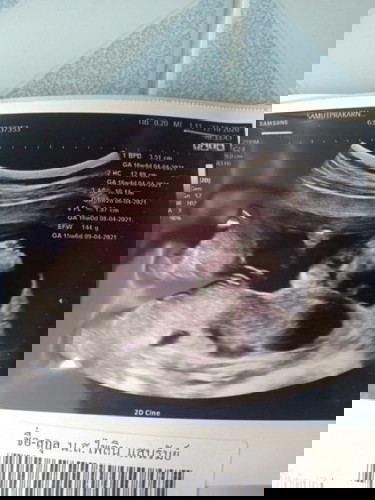

คุณหมอซาวด์ให้วันนี้16วีค ยังไม่เห็นเพศน้องเลยจร้า แบบนี้ดูไม่ออกเลยจ้า แม่ๆคนไหนพอดูออกบ้าง. ทางนี้ดูไม่ออกเลย555 แล้วผลตรวจเลือดแม่ออกมา แม่เป็นพาหะธาลัสซีเมีย แฟนปกติ แม่ๆค่ะ ถ้าแบบนี้อันตรายมากหรือป่าวค่ะ หมอบอกขาดธาตุเหล็ก ดีไม่ดีจะได้เข้าเลือดด้วย ค่าเลือดแม่เจาะรอบแรก31 รอบสองเหลือ23เอง แล้วเดือนหน้าคุณหมอก็นัดเจาะอีก2-3รอบ เลยค่ะ ตอนนี้กลัวมากจ้า สอบถามแม่ที่เคยมีประสบการณ์เป็นพาหะธาลัสซีเมียหน่อยค่ะ น่ากลัวมากมั๊ย #ขอคำแนะนำหน่อยค่ะ #ท้องแรก